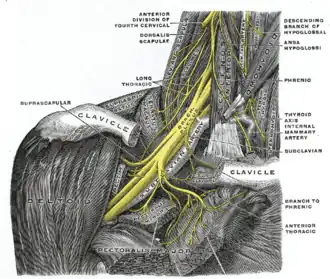

| The right brachial plexus with its short branches, viewed from in front. | |

Parsonage–Turner syndrome, also known as acute brachial neuropathy and neuralgic amyotrophy and abbreviated PTS, is a syndrome of unknown cause; although many specific risk factors have been identified (such as; post-operative, post-infectious, post-traumatic or post-vaccination),[4] the cause is still unknown. The condition manifests as a rare set of symptoms most likely resulting from autoimmune inflammation of unknown cause of the brachial plexus.[5]

Parsonage-Turner involves neuropathy of the suprascapular nerve in 97% of cases, and variably involves the axillary and subscapular nerves. As such, the muscles usually involved are the supraspinatus and infraspinatus, which are both innervated by the suprascapular nerve. Involvement of the deltoid is more variable, as it is innervated by the axillary nerve.[8]